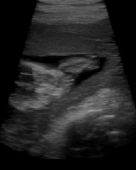

6. 4DUS – 4-Dimensional Ultrasound

4DUS – 4-Dimensional Ultrasound

The main objective of this project is the improvement of real ultrasound data of the human heart. The spatial representation of the heart in-vivo ...